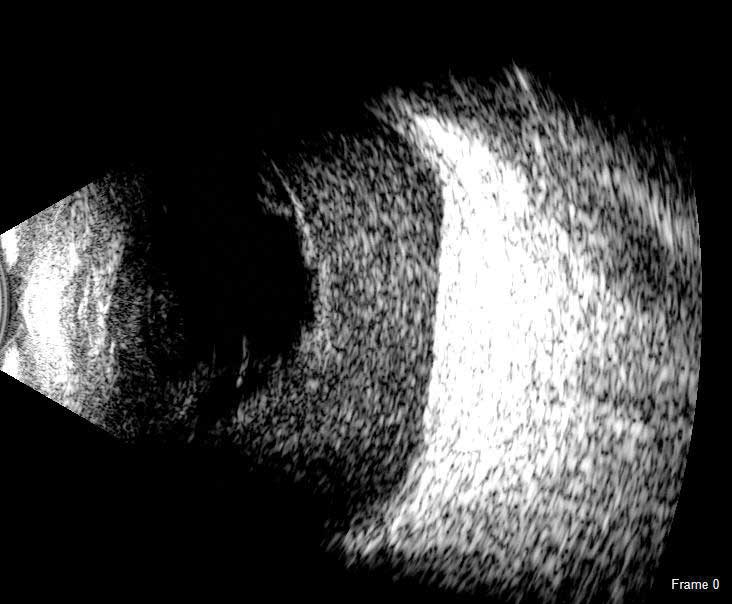

B-Scan

The redesigned B-Scan Probe, new with the Flex, provides clear imaging of the posterior segment of the eye, even when optical clarity is compromised.

The Scanmate Flex B-Scan probe enables clinicians to capture clear and precise images and videos of the posterior segment of the eye. Ultrasonic B-scans are effective, even when opacities (such as dense cataract, blood, or anatomical structures) are present which obscure optical technologies.

The B-Scan probe is available in both 12.5 MHz and 20 MHz frequencies. Among the on-screen tools are calipers to measure structures, an area measurement tool and an annotation tool that gives you a way to indicate pathologies on the image.

B-Scan Diagnostic Applications

The Flex B-Scan delivers clear images of the posterior portion, even when optical clarity is compromised. B-Scan imaging can aid the evaluation of:

- Retinal Detachments

- Vitreous Detachments

- Vitreous Humor Pathologies

- Staphylomas

- Posterior Segment Pathologies

- Choroidal Pathologies

- Optic Nerve Pathologies

- Scleral Thickening